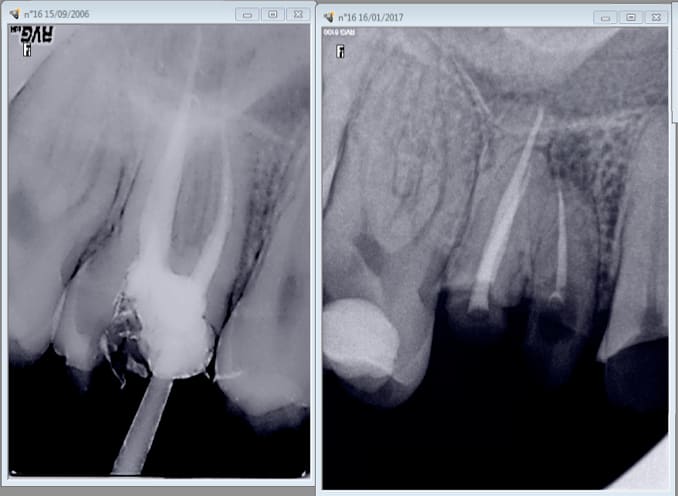

chicot29 écrivait:

------------------

> Si justement. C'est bien le mv2 non traité. -)

>

> Quand je vais la virer c'est ce que révèlera l'autopsie de cette racine. -)

> mais bon ca aurait pu etre plus grave si j'avais fait une couronne dessus hein

> casa ? -)))

Quand on parle du loup. -)))

Merde endo et couronne faites en 2011 pèche en 2017.

Quizzzzz : c'est la faute à pas de digue ? -))))

Il n'y aurait pas un mv2 ?

Ben si. Finalement, c'est une erreur de traiter le MV2 en première intention car on ne risque pas de déposer la couronne et d'en refaire une autre. -))

Hormis les peintures canalaires le MV2 non traité est la principale source source de 4ième. -)))

Quand il n'y a pas de pèche c'est que le plus souvent MV1 et MV2 sont en Y.